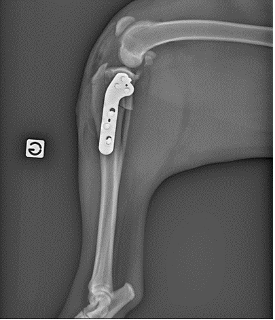

Le gold standard chez le chien passe par une intervention chirurgicale, appelée TPLO (nivellement du plateau tibial), qui modifie la conformation du genou afin de neutraliser la poussée tibiale crâniale. L’orientation des forces qui s’exercent sur le genou sont modifiées avec la chirurgie et permettent une stabilisation dynamique du genou. Cette intervention passe par une ostéotomie, stabilisée à l’aide d’une plaque et de vis.

Un suivi et une rééducation adaptée se font généralement sur 6 à 8 semaines.